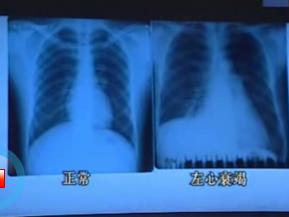

竇性停搏治療討論:胺碘酮作為Ⅲ類抗心律失常藥物,兼有輕度阻滯鈉,L型鈣通道和非競爭性岷外受體作用,對於器質性心臟病合併的心律失常,其作用明顯優於其他抗心律失常藥,有心功能不全則為首選。可延長心房肌,心室肌及傳導系統的動作電位和有效不應期,抑制房室結,竇房結的功能,體表心電圖表現上PR及QT間期的延長,使房顫轉為竇性心律。